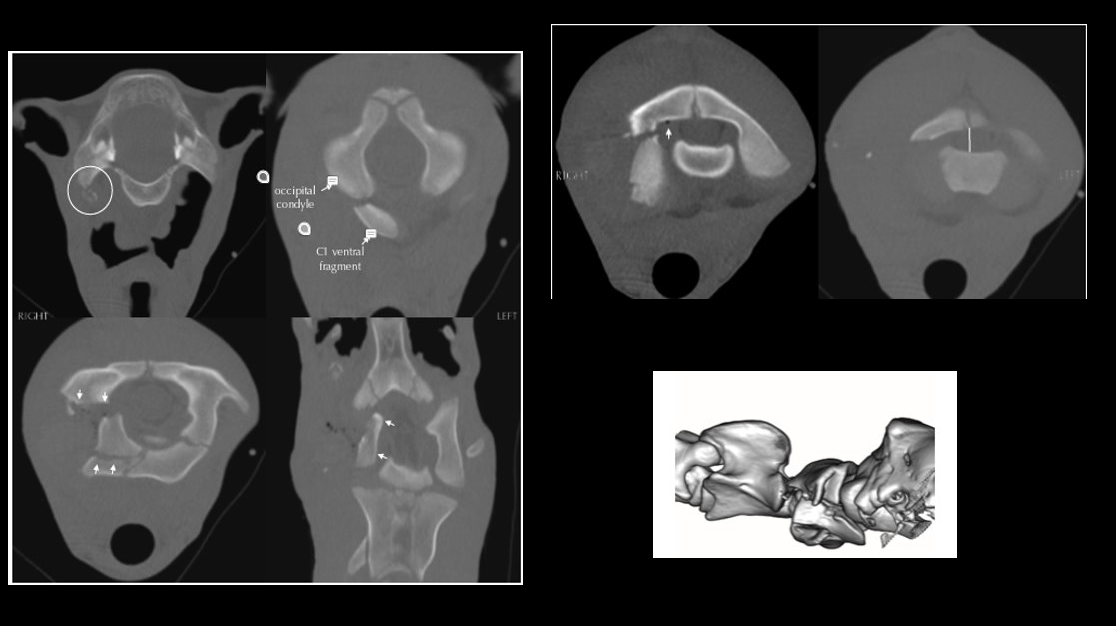

Case Example: 17‑Year‑Old Quarter Horse Gelding, Courtesy of UW Large Animal Hospital

The gelding was referred for worsening swelling, pain, and dysfunction of the left temporomandibular joint (TMJ). Clinical signs included lethargy, reduced feed intake, difficulty chewing hay, and marked sensitivity over the affected area.

Presentation

The gelding exhibited significant facial swelling, heat, and pain on palpation of left TMJ. He chewed hay slowly and occasionally quidded, though soft feed intake was normal. Initial diagnostics showed severe synovial inflammation and bacterial infection of the left TMJ. Evaluation of the contralateral TMJ was within normal limits.

CT Findings

• CT demonstrated severe left septic TMJ arthritis, left condylar osteomyelitis

• Chronic nondisplaced fracture with osseous sequestration, left otitis media, and Grade 3 bilateral temporohyoid osteoarthropathy.

• Incidental focal sclerosis of the left occipital condyle and atlas were also present.

Despite arthrotomy and lavage of the left TMJ, together with systemic and local antimicrobial therapy, the infection progressed and resulted in a grave prognosis. Left mandibular condylectomy was considered but deemed unlikely to restore comfort due extensive osteomyeltis extending into the stylohyoid bone of the left side.  Humane euthanasia was ultimately elected.